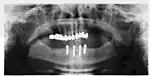

Implant retained fixed bridge or implant supported bridge

An implant supported bridge (or fixed denture) is a group of teeth secured to dental implants so the prosthetic cannot be removed by the user. They are similar to conventional bridges, except that the prosthesis is supported and retained by one or more implants instead of natural teeth. Bridges typically connect to more than one implant and may also connect to teeth as anchor points. Typically the number of teeth will outnumber the anchor points with the teeth that are directly over the implants referred to as abutments and those between abutments referred to as pontics. Implant supported bridges attach to implant abutments in the same way as a single tooth implant replacement. A fixed bridge may replace as few as two teeth (also known as a fixed partial denture) and may extend to replace an entire arch of teeth (also known as a fixed full denture). In both cases, the prosthesis is said to be fixed because it cannot be removed by the denture wearer.[15]